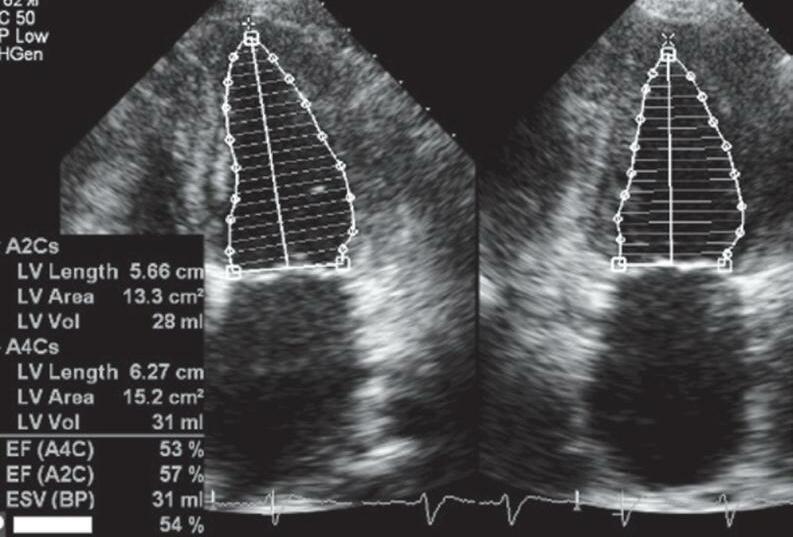

18 O Ecocardiograma no Manejo do Paciente Crítico, 193 Rodrigo Ferraz Salomão • Flávia Guimarães Brasil • Eduardo Boetner